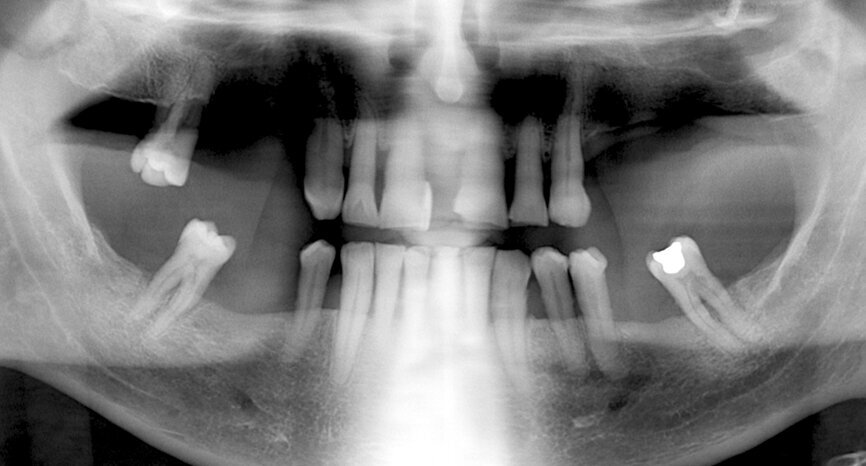

A 68-year-old patient with no medically relevant history and hopeless dentition was referred by his periodontist. A panoramic radiograph and dental CT scan were taken to evaluate the bone availability, disposition and density (Figs. 1 & 2). After the different treatment options were discussed, and in view of the patient’s overall dental, social and financial situation, an implant treatment with a same-day fixed temporary restoration was the first choice for both the dental team and the patient.